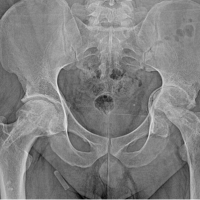

Patellar tendon rupture was diagnosed and confirmed by an abnormally high patella on X-rays and by echography, which showed a complete tendon rupture with a 32 mm gap between the two tendon sides. Patient consent for surgical treatment was obtained, and surgery was performed 7 days after the trauma.